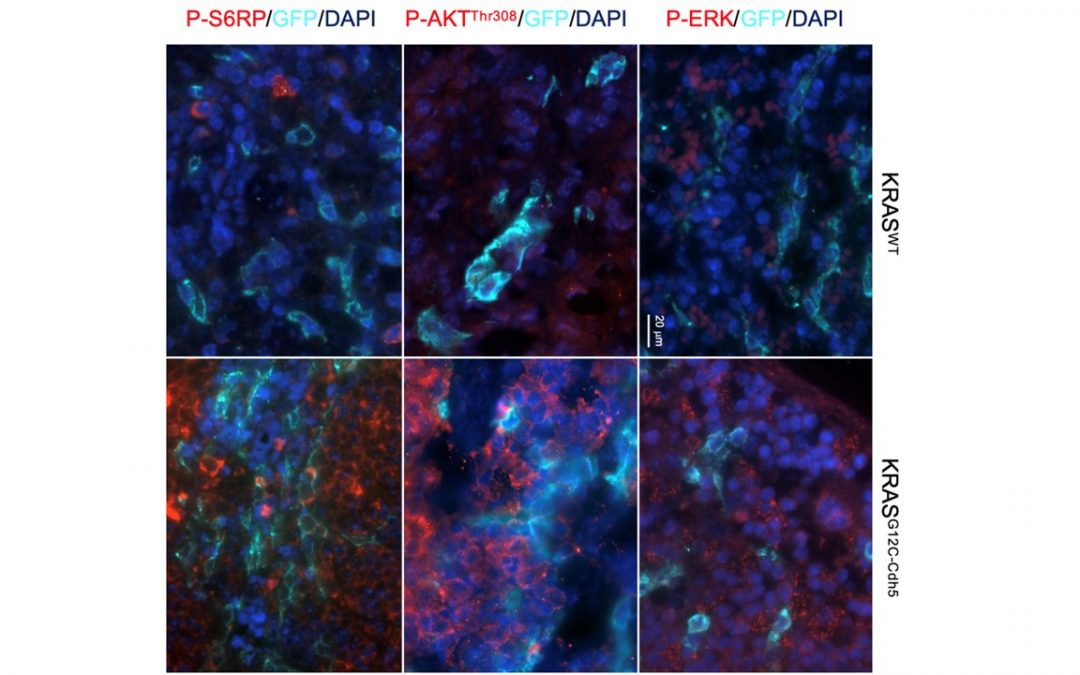

![[Syndrome de Cloves] Quand l’étude d’une maladie rare permet d’avancer sur des maladies plus répandues](https://wordpress-test.app.u-pariscite.fr/wp-content/uploads/2024/06/Lupus_Nephritis_2-Canaud-1-1080x675.jpg)

18 juin 2024 | Recherche Santé

L’équipe de recherche Médecine Translationnelle et Thérapies Ciblées, dirigée par le professeur Guillaume Canaud à l’Institut Necker-Enfants Malades (Université Paris Cité, AP-HP, Inserm), internationalement reconnue pour avoir identifié l’alpelisib comme traitement...